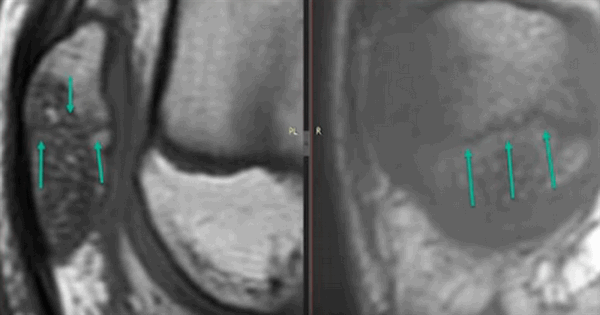

МР-скан коленного сустава в Т1 режиме (стрелкой указан костный отек)

При МРТ получают серии монохромных снимков анатомической области в аксиальной, сагиттальной и фронтальной плоскостях. При изучении изображений врач видит контуры различных элементов сочленения. Расшифровка МРТ-снимка коленного сустава подразумевает оценку сканов в сравнении с нормой. МР-томограммы называют срезами, поскольку изображения производят послойно, с шагом 1-2 мм. Врач последовательно изучает анатомическую зону на предмет соответствия всех структур норме. В процессе расшифровки фото обращают внимание на качество визуализации элементов, четкость контуров, присутствие зон измененного МР-сигнала (гипер- или гипоинтенсивного) в различных режимах сканирования (Т1 ВИ, Т2 ВИ, ДВИ, подавление жира).

МР-снимок коленного сустава в режиме Т2, контузия кости